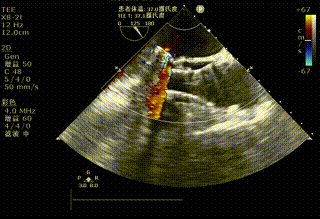

Step 6.超声观察:人工瓣膜位置、压差、密封良好,二尖瓣开合正常。

11.png

平均压差由术前43mmHg降至7mmHg,术前导管压差45mmHg,术后导管压差3mmHg;左心室收缩功能稳定,跨瓣压差显著改善,患者循环状态平稳。